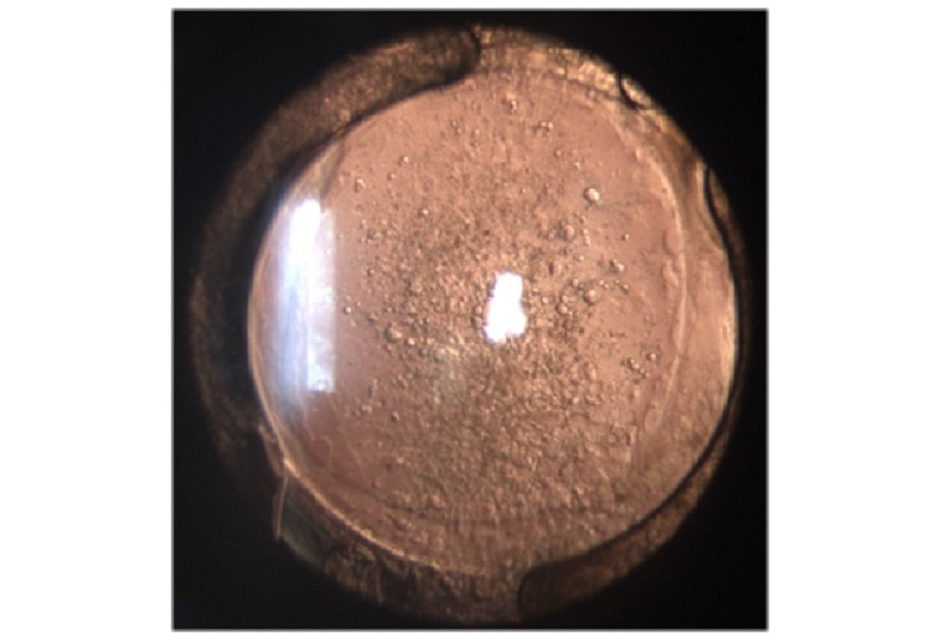

Assisting for Nd YAG Capsulotomy

This lesson includes the concepts of YAG Capsulotomy